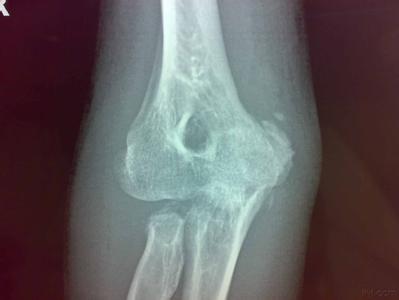

2.其他辅助检查 在3~6周后,X线摄片可见到骨化影。开始呈云雾状环状钙化,以后逐渐轮廓清楚,中央透亮。成熟后外周骨化明显致密,其内为骨小梁。

辅助检查:X线片见骨化影,开始呈云雾状环形钙化,以后逐渐轮廓清楚,中央透亮。数月后骨化,关节功能受限,应考虑本病。